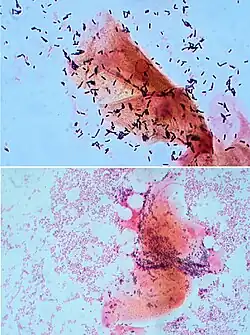

There are broadly speaking two different types of cell wall in bacteria, that classify bacteria into Gram-positive bacteria and Gram-negative bacteria. The names originate from the reaction of cells to the Gram stain, a long-standing test for the classification of bacterial species.[85]

Gram-positive bacteria possess a thick cell wall containing many layers of peptidoglycan and teichoic acids. In contrast, Gram-negative bacteria have a relatively thin cell wall consisting of a few layers of peptidoglycan surrounded by a second lipid membrane containing lipopolysaccharides and lipoproteins. Most bacteria have the Gram-negative cell wall, and only members of the Bacillota group and actinomycetota (previously known as the low G+C and high G+C Gram-positive bacteria, respectively) have the alternative Gram-positive arrangement.[86] These differences in structure can produce differences in antibiotic susceptibility; for instance, vancomycin can kill only Gram-positive bacteria and is ineffective against Gram-negative pathogens, such as Haemophilus influenzae or Pseudomonas aeruginosa.[87] Some bacteria have cell wall structures that are neither classically Gram-positive or Gram-negative. This includes clinically important bacteria such as mycobacteria which have a thick peptidoglycan cell wall like a Gram-positive bacterium, but also a second outer layer of lipids.[88]

Classification by staining

The Gram stain, developed in 1884 by Hans Christian Gram, characterises bacteria based on the structural characteristics of their cell walls.[187][85] The thick layers of peptidoglycan in the "Gram-positive" cell wall stain purple, while the thin "Gram-negative" cell wall appears pink.[187] By combining morphology and Gram-staining, most bacteria can be classified as belonging to one of four groups (Gram-positive cocci, Gram-positive bacilli, Gram-negative cocci and Gram-negative bacilli). Some organisms are best identified by stains other than the Gram stain, particularly mycobacteria or Nocardia, which show acid fastness on Ziehl–Neelsen or similar stains.[188]

Classification by culturing

Culture techniques are designed to promote the growth and identify particular bacteria while restricting the growth of the other bacteria in the sample.[189] Often these techniques are designed for specific specimens; for example, a sputum sample will be treated to identify organisms that cause pneumonia, while stool specimens are cultured on selective media to identify organisms that cause diarrhea while preventing growth of non-pathogenic bacteria. Specimens that are normally sterile, such as blood, urine or spinal fluid, are cultured under conditions designed to grow all possible organisms.[126][190] Other organisms may need to be identified by their growth in special media, or by other techniques, such as serology.[191]